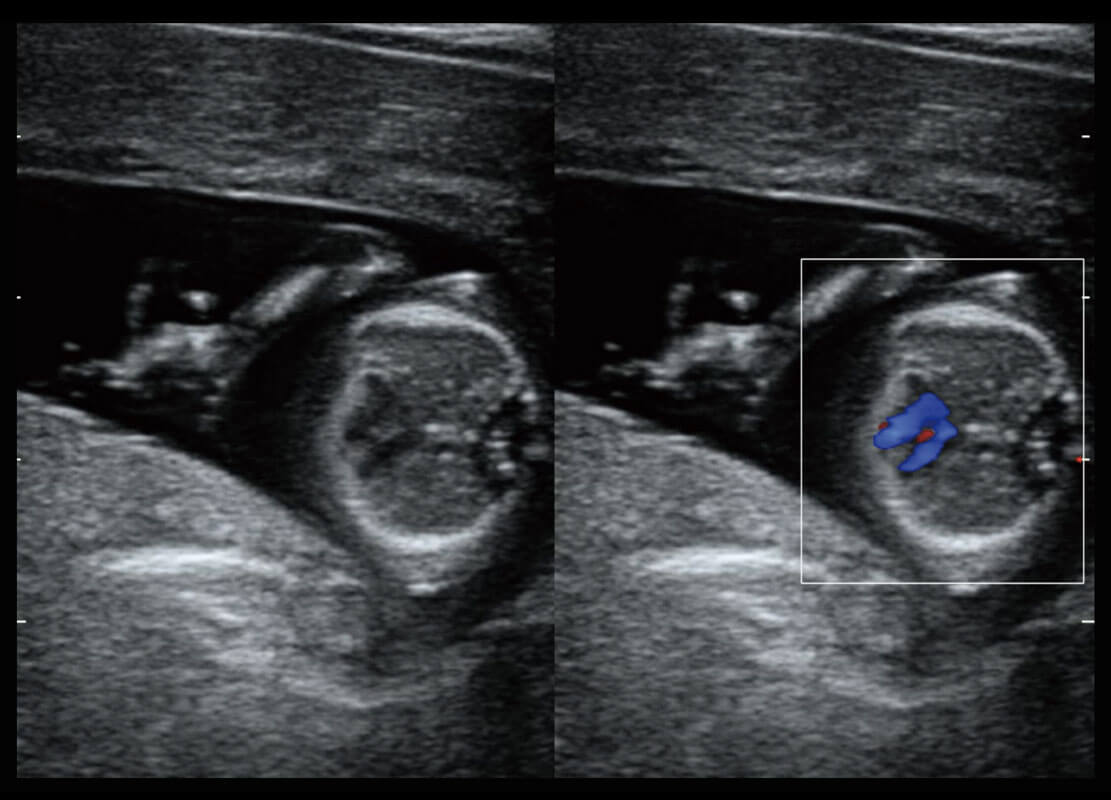

胎心筛查

P60搭载一系列胎儿心脏成像技术,实现精细的胎儿心脏评估。

• 四腔切面

• 四腔心血流